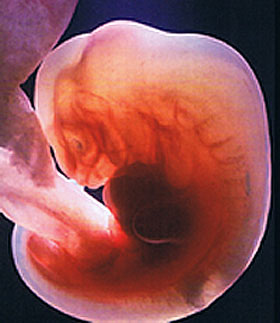

Jeśli jest czwarty tydzień położniczy, jest za wcześnie, aby mówić o płodzie. Zygota stopniowo przechodzi w stadium zarodka. Teraz nienarodzone dziecko jest prawie niewidoczną bryłą komórek, którą naukowcy nazywają morula. Pod mikroskopem będzie wyglądać jak jagoda pokryta „pryszczami”. Jeśli konsolidacja moruli w jamie macicy jeszcze nie nastąpiła, z pewnością nastąpi. I wtedy zaczyna się prawdziwa magia komórkowa.

Wielkość przyszłego płodu w 4. tygodniu położniczym jest porównywalna z „makiem”. Jego waga wynosi około 0,5 g, a wysokość 0,36–1 mm. Są to jednak dosłownie dane chwilowe. Zarodek szybko rośnie z powodu stałego podziału komórek.

Struktura zarodka

Lekarze często używają koncepcji krążka zarodkowego, który tworzy liść zarodkowy. Są to specjalne warstwy komórek:

- warstwa wewnętrzna (endoderma) spowoduje powstanie przewodu pokarmowego, wątroby i płuc, a także trzustki;

- środkowa warstwa (mezoderma) to przyszłe nerki, mięśnie, serce i naczynia krwionośne, a także szkielet dziecka;

- warstwa zewnętrzna (ektoderma) odpowiada za tworzenie układu nerwowego, głowy (w tym oczu, zębów i włosów), a także skóry.